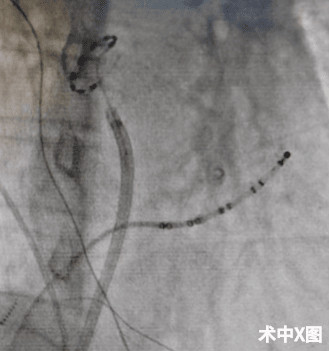

1个月前,王大爷在全麻下进行了手术。随着王大爷沉沉的睡去手术开始,电生理标测到王大爷的肺静脉里传出了许多杂乱无章的电信号,就像是在安静的湖面上掷入许多石子,这些石子产生的涟漪彼此影响,让心房电无序的传导,心脏没有规律的跳动。术中,随着脉冲电场不断的释放能量,这些混乱的电信号肉眼可见地快速湮灭。术毕,电生理标测到王大爷的心房又恢复了安静。王大爷手术后迅速康复,至今再未出现房颤发作,他又可以像往常一样和老伴出去散步,和老友下棋,惬意地享受退休后宁静的生活。

目前的房颤消融手术方式中,射频消融及冷冻消融是主流的手术方式。而最新的房颤脉冲电场消融(PFA)则通过在短时间内将高电压脉冲作用于细胞膜的磷脂酸分子层,导致跨膜电位形成,从而产生不稳定电势,使细胞膜形成不可逆的穿透性损伤,产生纳米级的孔隙,从而导致细胞膜渗透率的变化,破坏细胞内环境稳态,最终导致细胞凋亡。脉冲电场消融具有组织特异性,简单说就是它能够清除掉产生异常电信号的病灶,而对正常的心脏传导系统、周围神经、心肌组织、食管等不会产生不可逆的损伤,同时由于其快速释放能量,也缩短了手术时长。